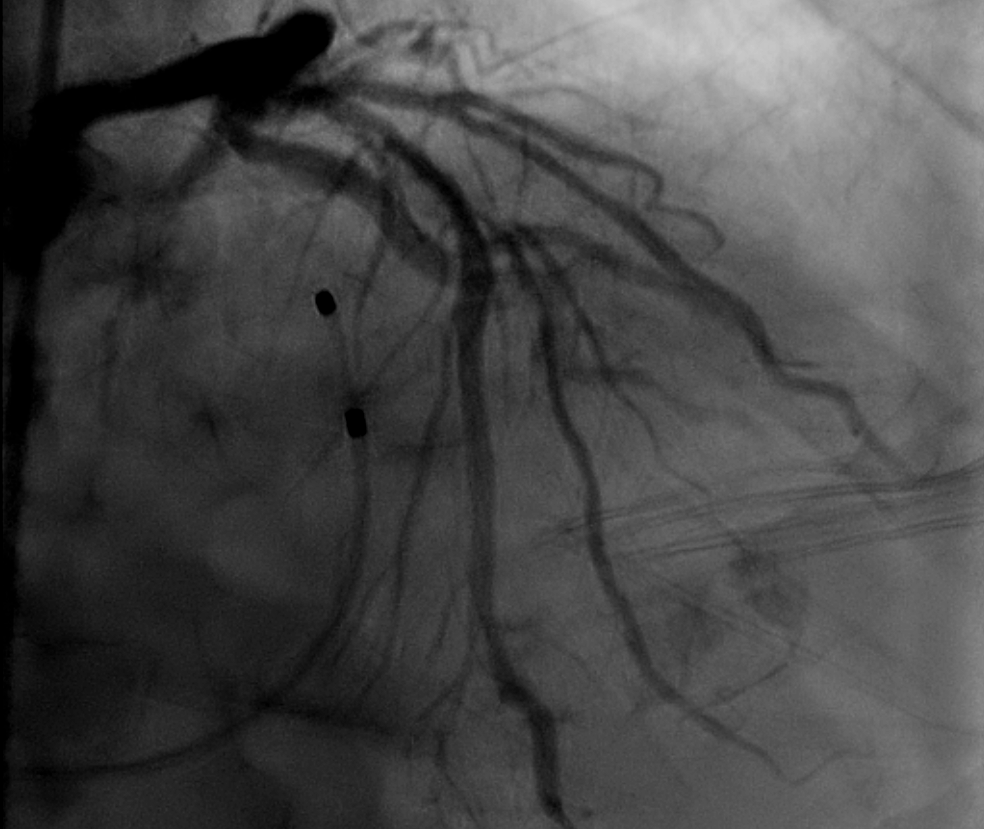

根部造影

三叶瓣,重度钙化,钙化主要分布在瓣叶游离缘,法式窦结构较大,双冠高度较高,升主动脉未见明显扩张,心脏角度40°,左室大小可,心肌肥厚,主动脉弓部走行较平缓,主动脉弓部可见钙化,过弓轻柔谨慎,以右侧股动脉为主入路。

唐熠达教授团队对病例进行多学科综合分析评估决定行一站式PCI+TAVI手术,结合患者91岁高龄,主动脉根部结构及双侧劲动脉粥样硬化斑块形成,脑动脉硬化情况采用20mm球囊预扩,拟植入VenusA-Valve L26瓣膜。